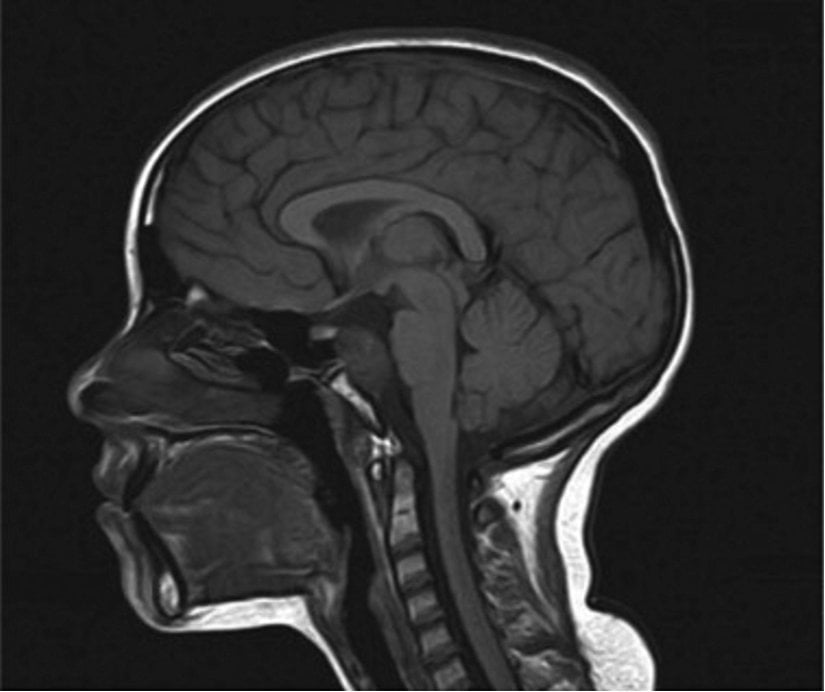

Bilinç öncesi sürecin nörolojik temellerini anlamak, bilişsel sinirbilimde çok önemli bir noktayı oluşturmaktadır. Çeşitli beyin yapıları ve ağları arasındaki karmaşık etkileşim, bilginin bilinçdışından bilinçli durumlara geçişini düzenleyerek bilinç öncesi bilişin dinamik manzarasını şekillendirir. Fonksiyonel nörogörüntüleme çalışmaları, özellikle fMRI ve EEG gibi teknikleri kullananlar; bilinç öncesi işlemlerle ilişkili sinirsel alt katmanların tanımlanmasına önemli ölçüde katkıda bulunmuştur.

Bilinç öncesi aktivitelerin sinirsel bağıntıları, genellikle amigdala ve hipokampüs gibi limbik sistem içindeki yapıları içerir ve duygusal ve hafızayla ilgili süreçlerin bu aktivitelere katılımını sağlamaktadır. Özellikle amigdala, duygusal olarak yüklü uyaranların bilinçli farkındalığa ulaşmadan önce hızlı bir şekilde değerlendirilmesi ve işlenmesinde çok önemli bir rol oynamaktadır. Aynı zamanda hipokampüsün olguların, olayların veya belirli bilgilerin bilinçli olarak hatırlanmasını içeren uzun süreli bellek türü olan bildirimsel anıların oluşumu ve geri getirilmesinde rol oynadığı, bilinç öncesi bilgilerin erişilebilirliğinde bir rolü olduğu öne sürülmektedir. Limbik sistemin ötesinde, karmaşık bağlantı kalıplarıyla prefrontal korteks; bilinç öncesi içeriğin bilinçli düşünceye entegrasyonunu düzenleyen önemli bir oyuncu olarak ortaya çıkmaktadır. Bilişsel süreçlerin izlenmesinde rol oynayan ön singulat korteks aynı zamanda bilinç öncesi aktivitelerin göstergesi olan aktivasyon modellerini de sergiler.

Bilinç öncesi işleme kavramı, otomatik ve kontrollü bilişsel sistemlerin paralel işleyişini vurgulayarak ikili işleme teorilerinin daha geniş çerçevesiyle uyumunu sağlar. Araştırmalar, bilinçaltı uyaranların bilinçli algının yokluğunda bile sinirsel tepkileri ortaya çıkarabildiğini ve sinir mimarisi içindeki bilinç öncesi süreçlerin özerkliğinin altını çizdiğini göstermektedir. Nörobilimsel araştırmalarla aydınlatılan subkortikal ve kortikal yapılar arasındaki dinamik etkileşim, bilinçdışından bilinçli zihinsel durumlara geçişi yöneten karmaşık mekanizmaları aydınlatarak bilinç öncesi bilişin sinirsel temelleri hakkında kapsamlı bir bakış açısı sunmaktadır.